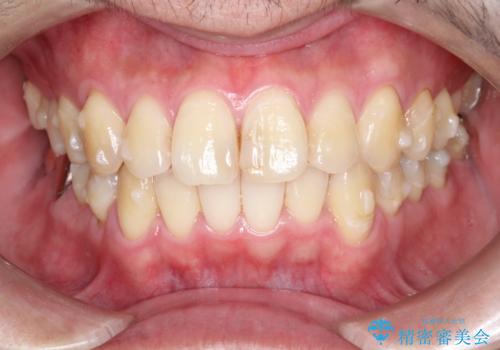

全体的ながたつきをインビザラインで改善

- 全体的ながたつきを主訴に来院されました。

歯と歯の間をわずかに削って、スペースをつくり並べる計画としました。

しっかりと、マウスピースの装着時間を守っていただいたので、スムーズに治療をおえることができました。